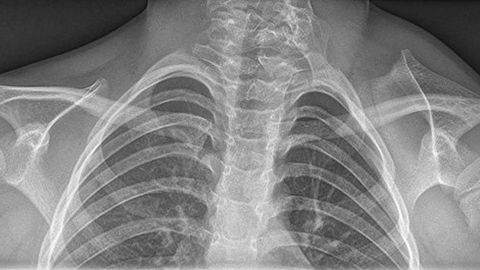

An X-ray image of the chest and shoulders showing sprengel's deformation.

0:05:19.7 RW: And the consequence is that the scapula on that side doesn't form normally. And it might be hypoplastic, that is, smaller than a normal scapula. Remember hypo means below, and plastic means shape. It turns out that if this happens to the scapula, then hypoplasticity will probably also affect all the muscles that attach to that scapula. And there are a few other things that we see with Sprengel's deformity as well. This condition often appears with some other musculoskeletal abnormalities, including Kliplofile syndrome, scoliosis and spina bifida. Kliplofile syndrome is a new one on me. This is an anomaly in which two or more cervical vertebrae are fused, and this leads to a really shortened neck and a limited range of motion and pain. I have included an artist's rendering of an MRI taken from a person who had both Sprengel's deformity and Kliplofile syndrome, so you can see how these situations affect the shoulder girdle. And of course you will find that in our show notes. Sprengel's syndrome is rare.